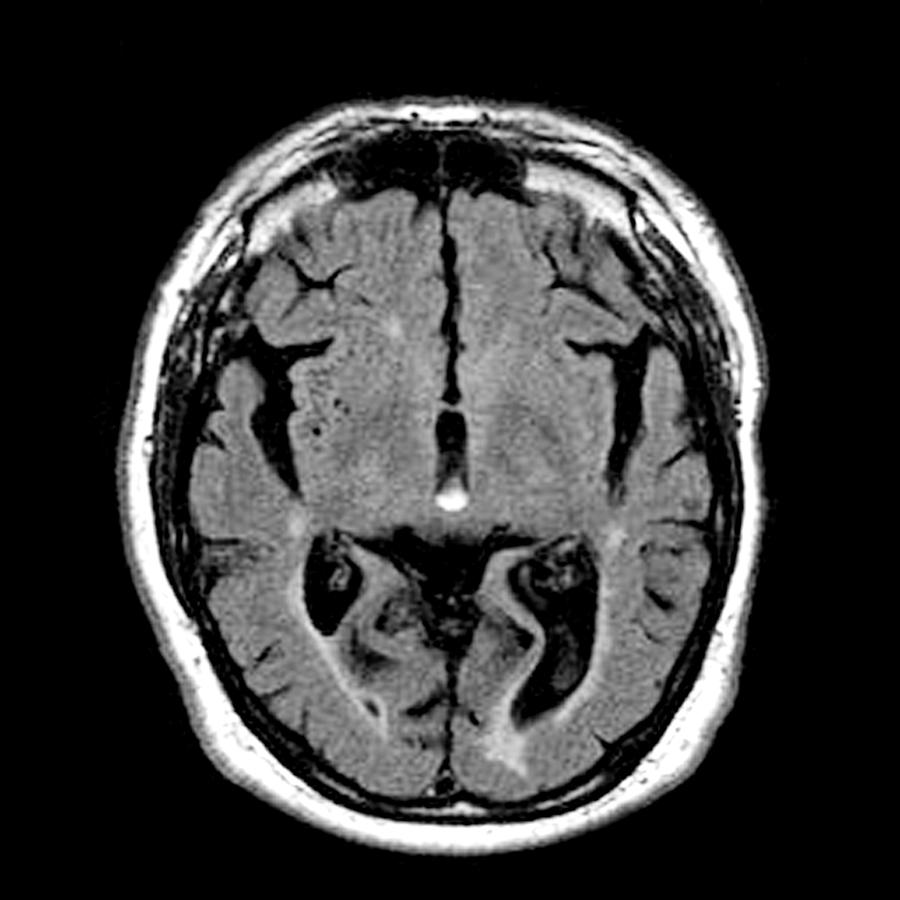

images of dementia brain

What Does The Brain Look Like With Dementia – DementiaTalkClub.com

Can Ct Scan Detect Alzheimers – Dementia Talk Club

Alcoholic Dementia, Mri Scan Photograph by Du Cane Medical Imaging Ltd

Alcoholic Dementia, Mri Scan Photograph by Du Cane Medical Imaging Ltd

Alcoholic Dementia, Mri Scan Photograph by Du Cane Medical Imaging Ltd

Dementia, MRI scans – Stock Image – M140/0433 – Science Photo Library

Ct Scan Alzheimer’s Vs Normal – DementiaTalkClub.com

Using MRI scans to reveal early signs of dementia | Health-RI

Dementia brain ct hi-res stock photography and images – Alamy

Dementia brain ct hi-res stock photography and images – Alamy

Dementia brain scan hi-res stock photography and images – Alamy

Dementia Brain Stock Photos & Dementia Brain Stock Images – Alamy